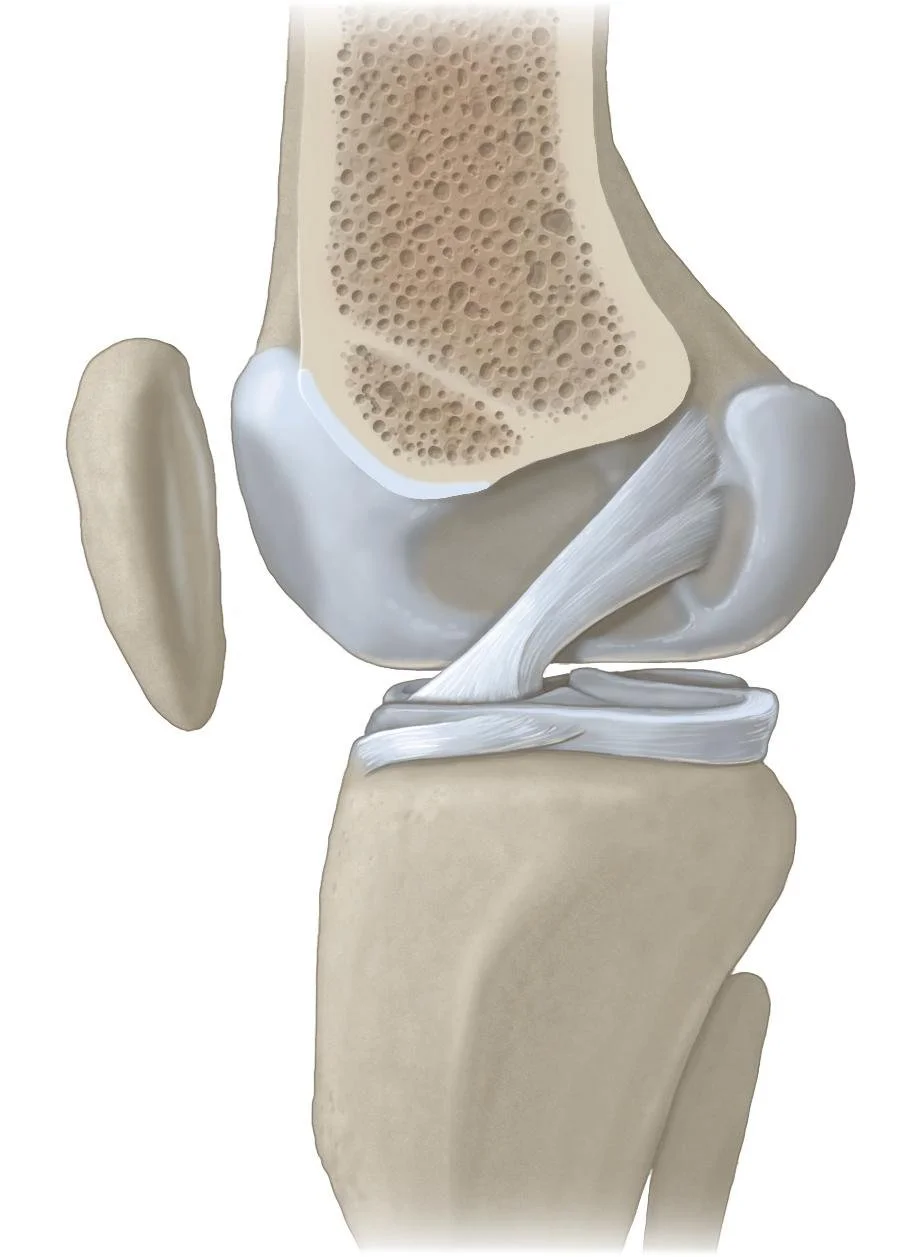

Medical Illustration

All images are works made for hire and are the exclusive property of the client. These are shown as sample purposes of my work only. For licensable work, please see my Illustration Services page.

Contract freelancer for many others, some examples of my work below.

Winner of Award of Excellence for Hockey Anatomy at the 2019 Association of Medical Illustrators Salon